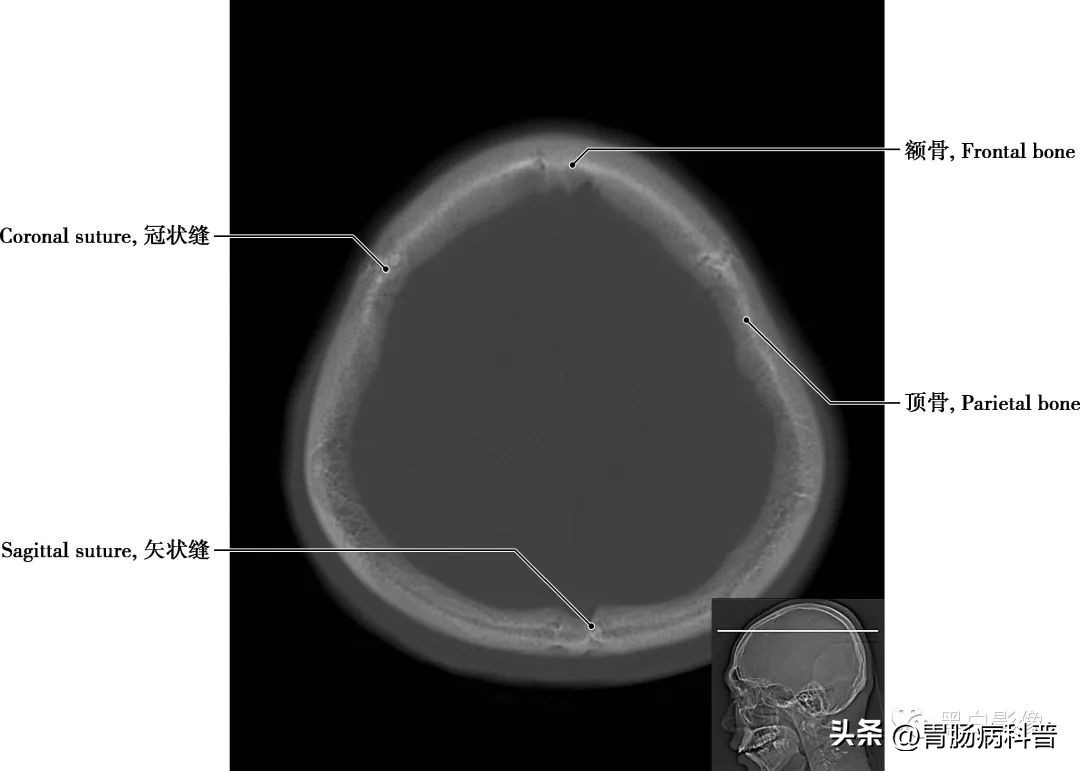

图1-2-1 经顶骨轴位切面

顶骨 位于颅盖的中部,左右各一,呈四边形,为外凸内凹典型的扁骨